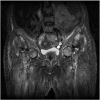

Simultaneous bilateral femoral neck fracture in a patient with renal osteodystrophy

We present a unique case of displaced simultaneous bilateral fractures, Garden 3 type, in a 49 year woman treated with non-cemented total hip arthroplasty. The patient showed a Harris hip score of 86 on the right hip and a 81 on the left side on the fourth postoperative year, besides a bilateral Trendelenburg gait, more pronounced on the right side. She needed a cane to walk, and felt pain in the left thigh. The X-ray showed a shortening of 0.9 cm and a left femoral varus. The other arthroplasty components showed good osseointegration and position. We found that the use of the uncemented total hip arthroplasty to treat a simultaneous bilateral fracture in renal osteodystrophy patients has satisfactory results at a four year follow-up. According to the OCEBM Levels of Evidence Working Group, this study is graded as a Level of Evidence IV.